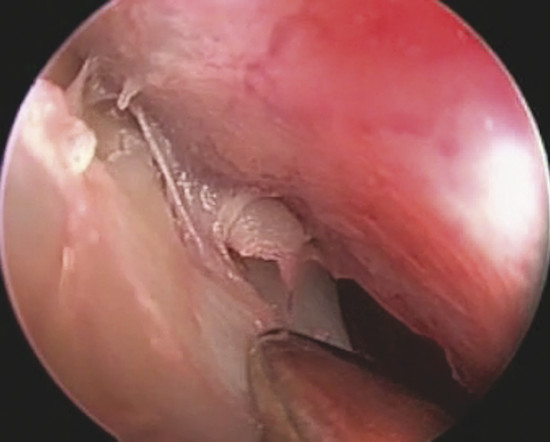

The perforation margins are then bilaterally trimmed and widely detached all around the perforation from the underlying cartilage or bone by a sickle knife to achieve a “refreshening of the edge” (Fig. 19‑1). It is important to elevate bilaterally an area of mucoperiosteum or mucoperichondrium of at least 1 cm all around the perforation.